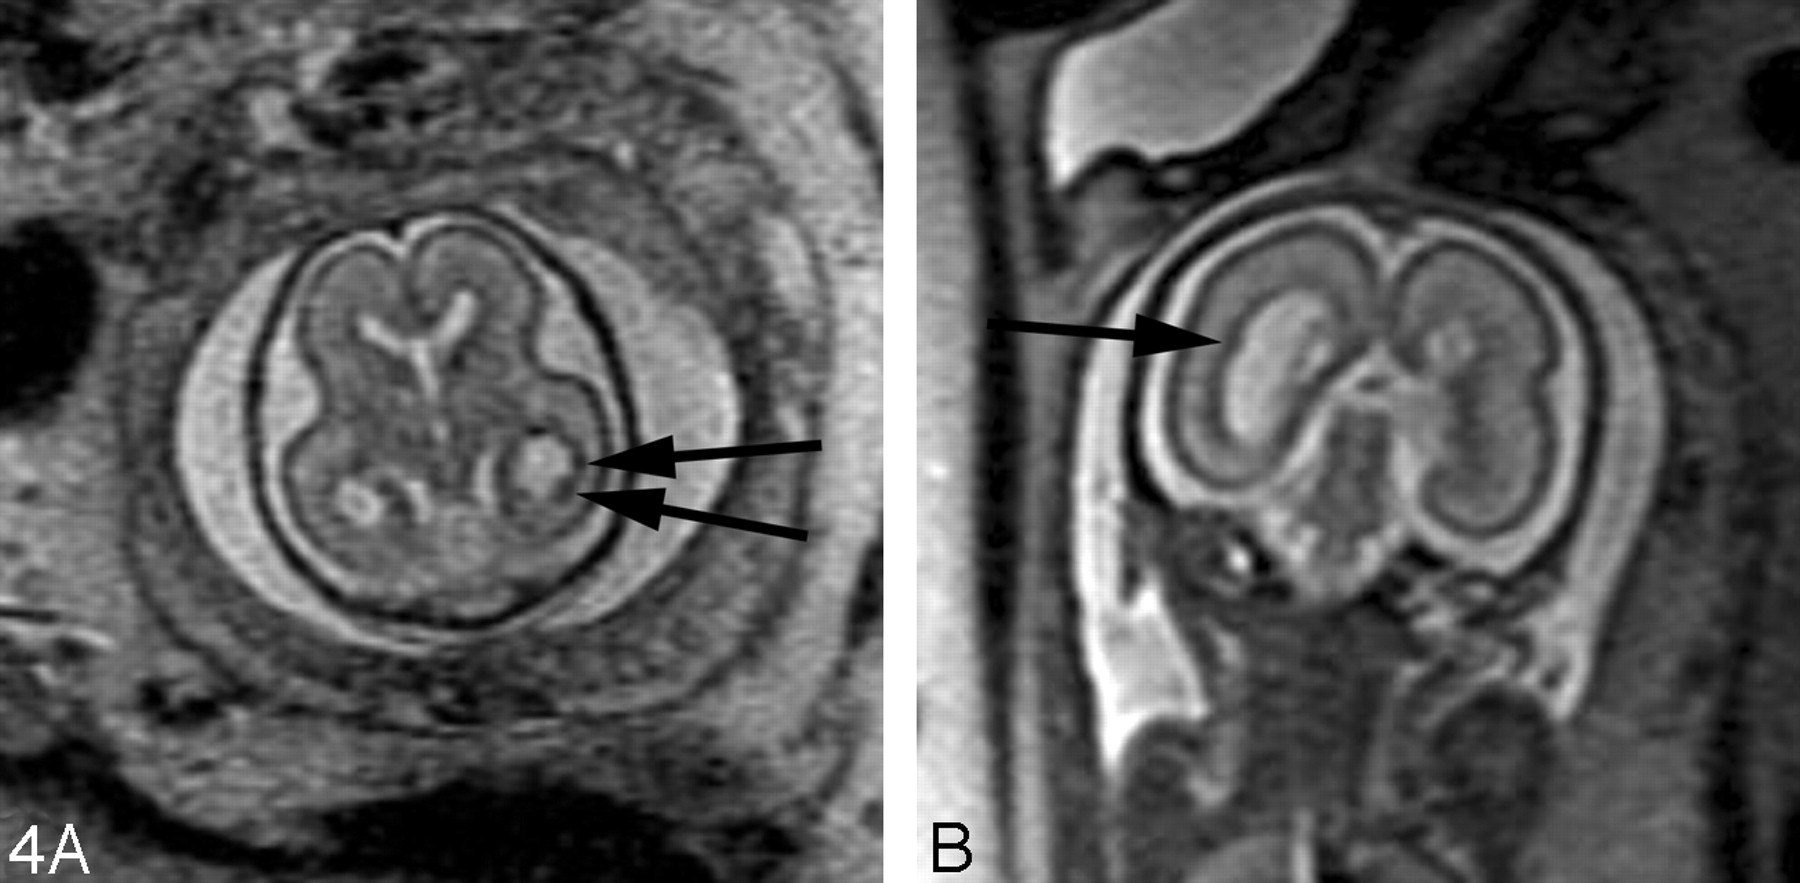

Destructive lesions generally appear as small periventricular areas of T2 hyperintensity, focal defects or irregularities in the germinal matrix, or larger areas of abnormal signal intensity (with or without volume loss) involving the developing white matter and overlying cortex (Fig 7). Subtle irregularities of the ventricular margin may also be an indication of injury to the adjacent germinal matrix and/or overlying developing white matter. Hemorrhage usually appears as a hypointense area on T2-weighted images and hyperintense area on T1-weighted images, though the signal intensity can vary depending on the stage of hemorrhage. Intraventricular hemorrhage can appear as debris layering in the dependent portion of the ventricle or as a focal hematoma (Fig 6B). The detection of small subependymal hemorrhages is more difficult, partly because the normal germinal matrix has similar signal intensity to blood (hypointense on T2-weighted images and hyperintense on T1-weighted images) because of its high cellularity (Fig 8). T2* weighted gradient-echo sequences may be useful to help to confirm the presence of blood, because the hemorrhage appears more hypointense than the germinal matrix.

Coronal ssFSE T2-weighted image in a 25-week old fetus demonstrates a focal area of T2 hyperintensity adjacent to the frontal horn of the left lateral ventricle (arrow). This was also confirmed on axial image (not shown) and is consistent with an area of parenchymal injury. The lateral ventricles are mildly dilated (measuring 12–13 mm on sonography).